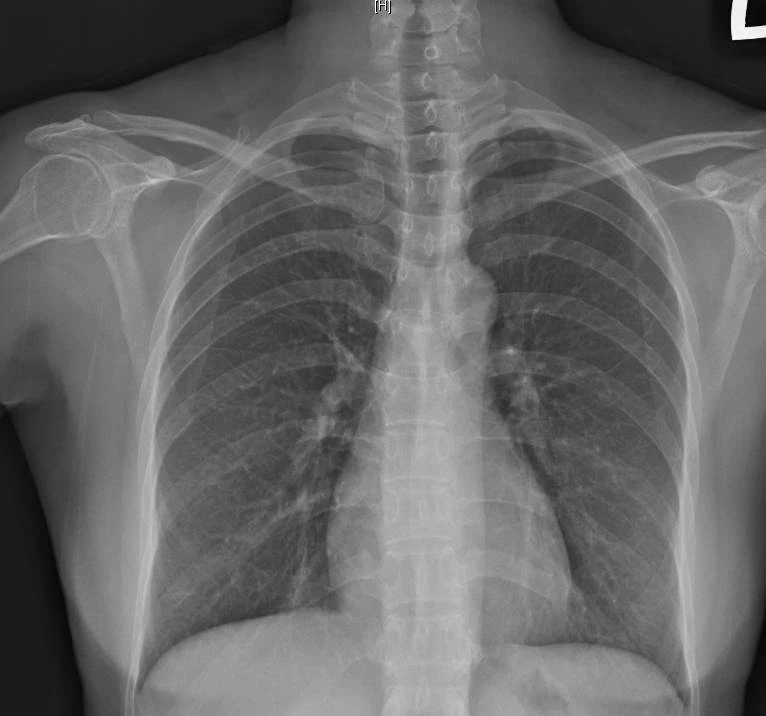

阮綜合舉例,高雄一名33歲KTV領班在農曆春節期間感冒後,雖主要症狀改善,仍持續乾咳近半個月,影響工作表現,被主管要求就醫;另有61歲家庭主婦春節自日本返台後感冒,發燒、喉嚨痛等症狀經治療緩解,但乾咳持續近1個月,經檢查胸腔X光未見肺炎或浸潤陰影,確診為感染後咳嗽。

蕭惠元提醒,若咳嗽期間出現痰轉黃綠且濃稠、咳血、再次發燒,或伴隨呼吸困難、胸悶胸痛及喘鳴聲,可能代表發炎惡化,須儘速就醫檢查,以排除肺炎、肺癌或肺結核等嚴重疾病。